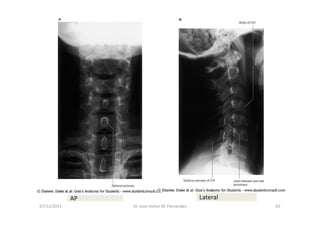

Anatomia Radiológica Cervical

1. Radiografia Simples

Radiografia da coluna cervical

Série de Radiografias Simples

da Coluna Cervical

• 1- Incidência AP com a boca aberta (para visualizar C1-C2);

• 2- Incidência AP cervical inferior;

• 3- Incidência cervical lateral (perfil);

• 4- Incidências oblíquas direita e esquerda;

• 5- Incidências adicionais:

- Incidência lateral em flexão e extensão

- Incidência de Fuch

- Incidência dos pilares de Boyleston

07/12/2015 Dr. José Heitor M. Fernandes 65

AP Lateral